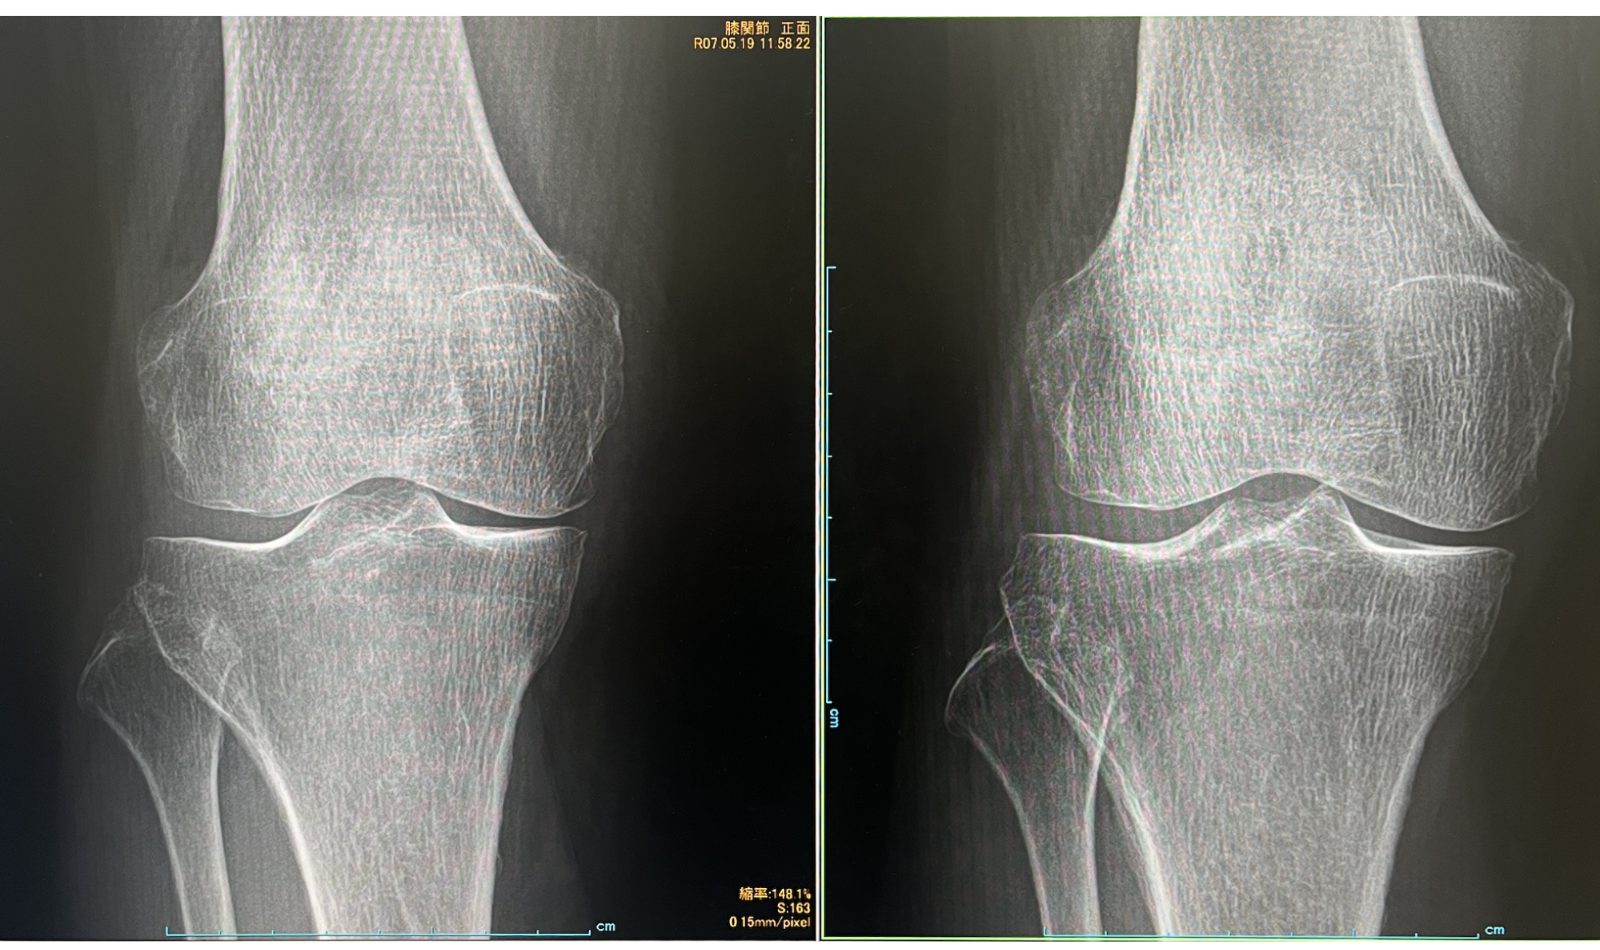

O脚が改善した73歳女性の症例紹介

現病歴:

2024年6月から右膝関節内側部痛が発症し、他院でヒアルロン酸注射などを行っていたが一向に良くならず。2025年5月に医療法人社団 東整会 東京神田整形外科クリニックの再生医療カウンセリングを受診する。

右変形性膝関節症と診断し、同日より右膝関節へ東整会式プレミアムエクソソームを開始した。

レントゲン評価:

治療前 治療後

治療結果:

ひざ痛がKOOS66.7⇒80.6まで改善し、日常生活での痛みがほぼ改善しました。さらにレントゲン評価にて関節裂隙が拡大した治療結果となりました。